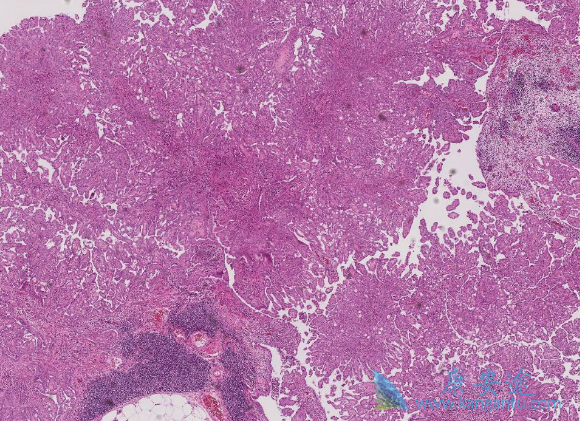

间皮瘤是一种罕见的恶性肿瘤,主要是由接触石棉引起。在美国,每年超过2000人被诊断为间皮瘤,而且确诊时大都为晚期。目前对于间皮瘤的治疗还没有标准疗法,医生只能根据每位患者的具体情况治疗治疗方法。虽然如此,此类患者的预后很差,一般术后中位生存期也大约在1年左右。也因此被称为恶性间皮瘤。